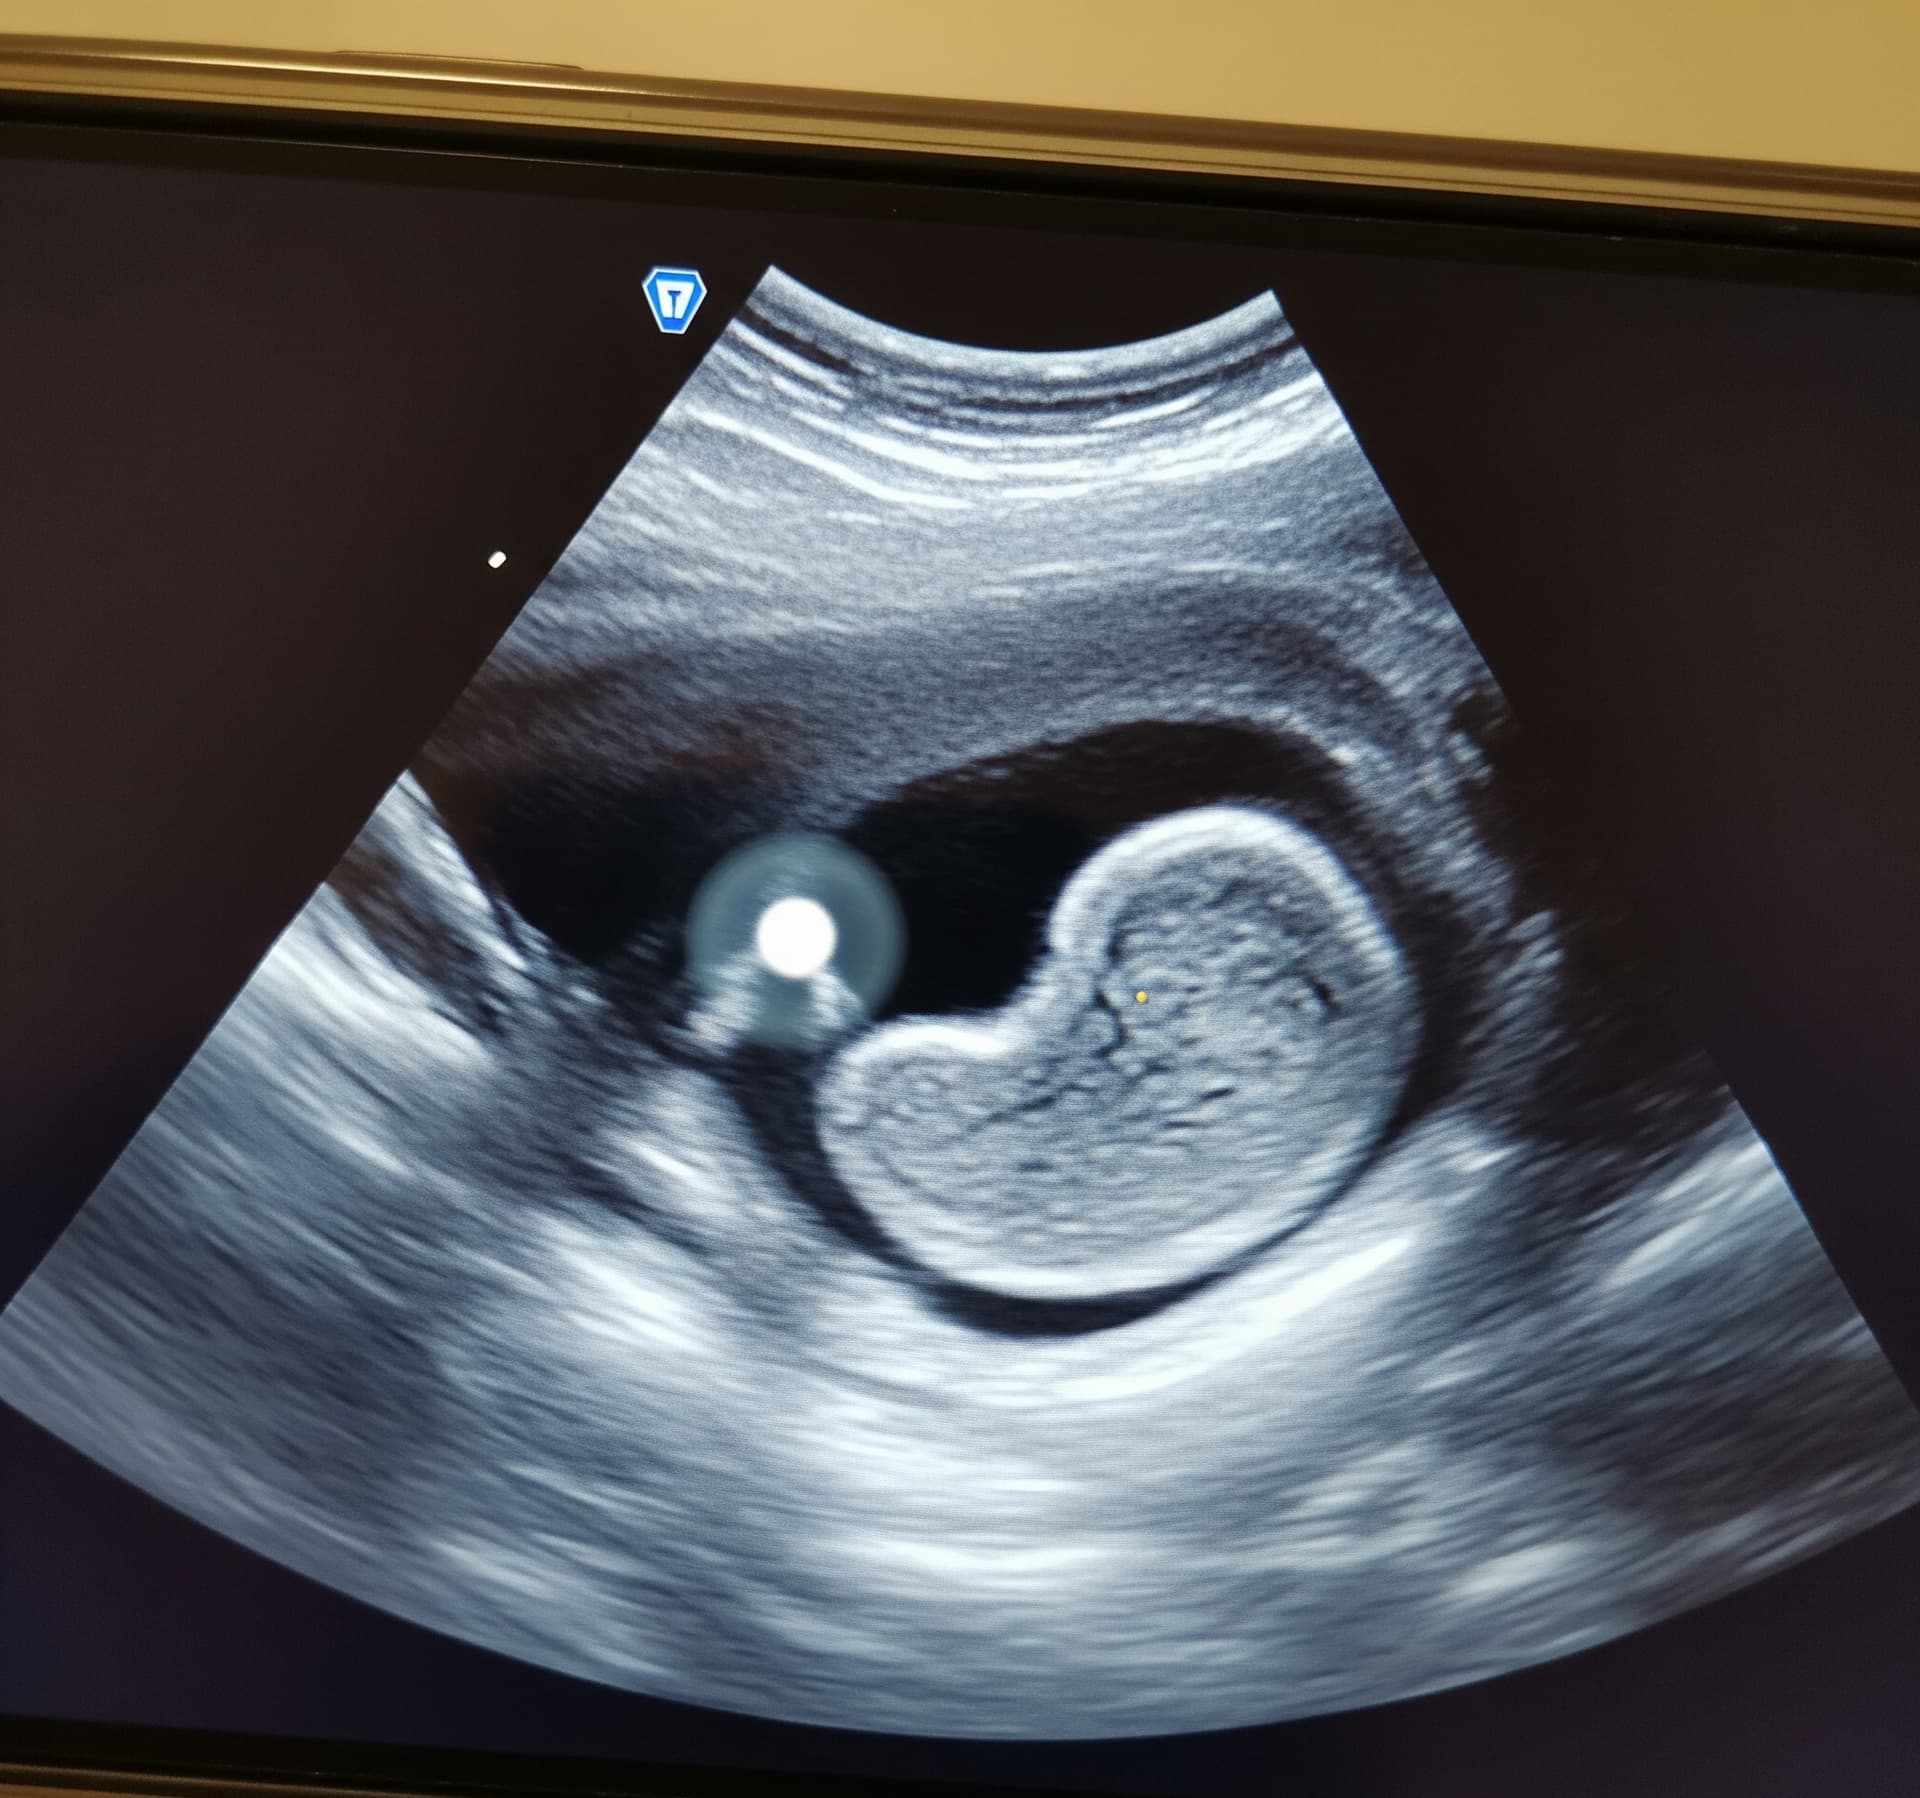

Pierwsze badania prenatalne to dla wielu mam bardzo emocjonujący moment – zobaczenie bijącego serduszka, pierwsze zdjęcie z USG… ale też czasem niepokój. Co jeśli lekarz powie, że „nie widać żołądka”? Brzmi poważnie, ale spokojnie – nie zawsze to oznacza coś złego. W tym artykule wyjaśniam, co może się za tym kryć i co warto zrobić w takiej sytuacji.

Brak widocznego żołądka na obrazie USG może mieć wiele przyczyn i wcale nie muszą one być niepokojące. Czasem wystarczy chwila, by wszystko się wyjaśniło.

Dziecko jeszcze nie połknęło płynu owodniowego żołądek staje się widoczny dopiero wtedy, gdy zacznie się on nim wypełniać.

Pozycja dziecka utrudnia ocenę jeśli maluch ułoży się „tyłem” do sondy, obraz może być niepełny.

Sprzęt i warunki badania jakość USG czy napięcie powłok brzusznych u mamy też mają znaczenie.

Wady rozwojowe np. problemy z przełykiem, które uniemożliwiają połykanie płynu owodniowego ale to tylko jedna z możliwości i diagnozuje się to dopiero po dalszej obserwacji.

Nie zawsze. Takie obserwacje są wskazaniem do ponownej oceny, ale nie są równoznaczne z diagnozą. W wielu przypadkach podczas kolejnego badania żołądek już jest widoczny i rozwój przebiega prawidłowo.